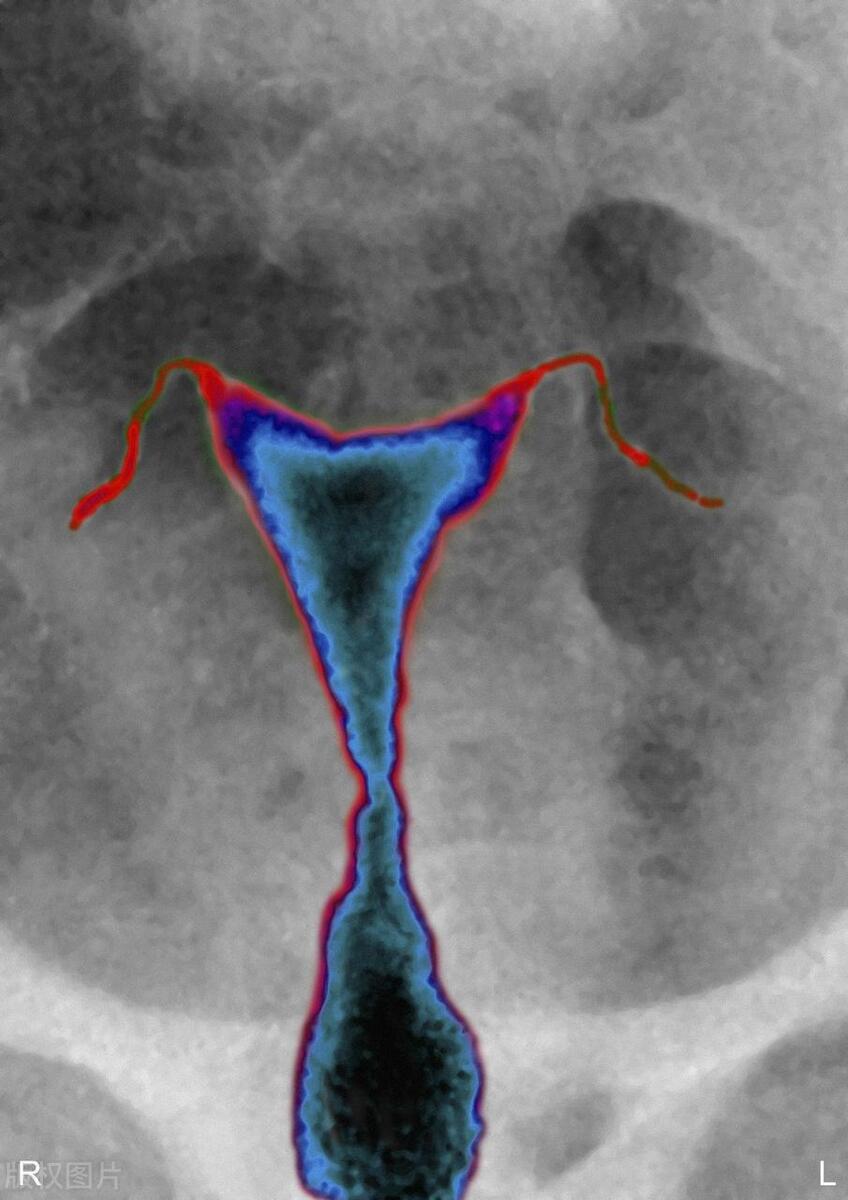

二、通常情况下,阴道上端与子宫、输卵管相连直通腹腔,下端则与外界直接相通,这是女性生殖器的独特之处。因此当出现生殖器官的炎症时,特别是在抵抗力、免疫力下降的时候,病菌可由阴道进入子宫,再通过输卵管进入卵巢、腹腔,导致盆腔炎症的产生。

因此,如情侣双方在经期同房,阴茎带至阴道的致病菌将会大量繁殖。这些致病的“集团”菌随即蜂拥上行,穿过子宫颈,进入子宫腔,并在子宫腔的创面上聚集。这些致病菌可黏附于精子表面进入输卵管,或由于房事时造成的负压而被“吸入”输卵管,就可能引起输卵管炎、导致粘连,以及管腔的堵塞。随之而来的严重后果是输卵管被阻塞后、精子不能通过阻塞部位,等候在这里的卵子也就不能受精、不孕症就此形成。有时输卵管阻塞较轻,精子可挤过狭缝到达输卵管外侧段使卵子受精、但比精子大十几倍的受精卵却不能通过狭缝进入子宫腔,于是只能就地种植于输卵管,这就造成了宫外孕。

4.感染性传播疾病,如不洁*生活性**、*交性**过频会导致病原体的入侵。女性的子宫内膜炎、输卵管炎、子宫内膜异位症等疾病甚至不孕症的高发生率,与不洁*生活性**有很大的关系。不洁*生活性**时,阴茎带至阴道大量的致病菌,这些致病菌随即上行,穿过子宫颈,进入子宫腔,通过输卵管可进入腹腔。